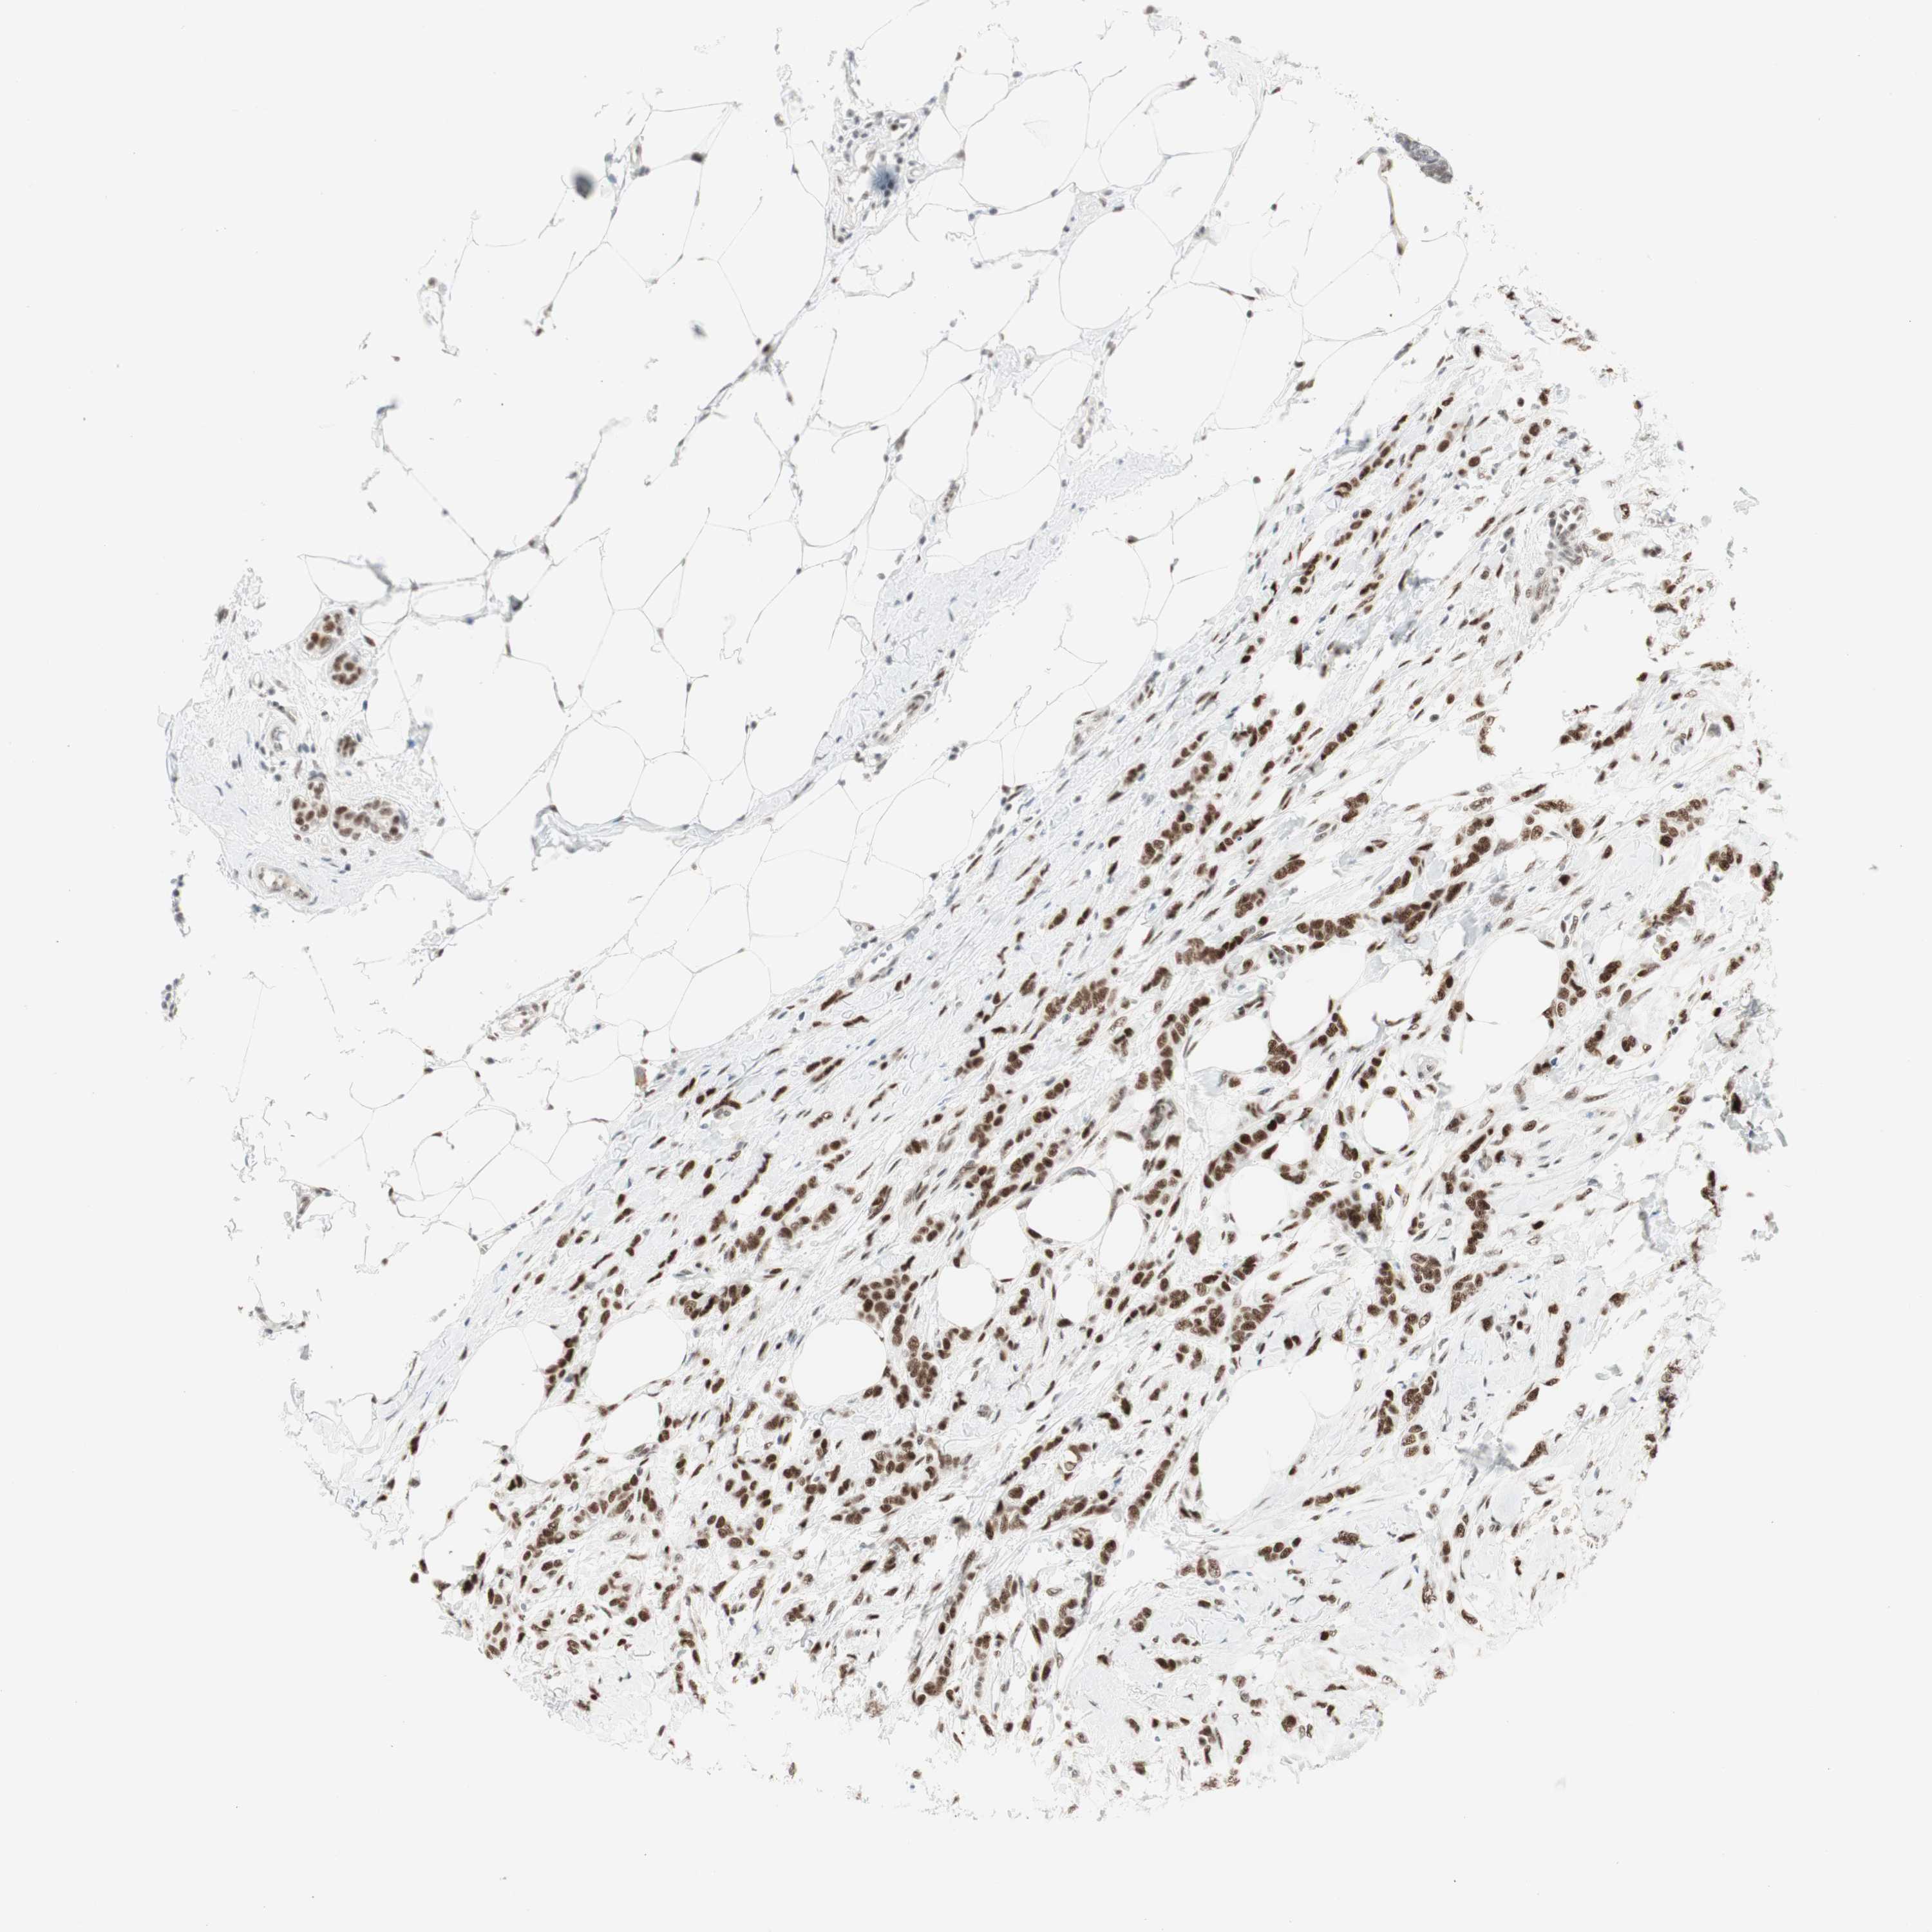

CANCER BREAST CANCER Show tissue menu

BRCA TCGA BRCA VALIDATION PROTEIN EXPRESSION